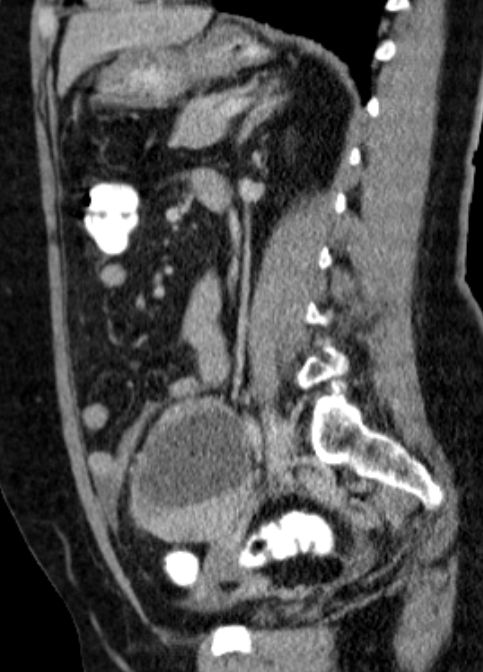

malignes Teratom 58-jährige Frau mit einen malignen Teratom mit Abszedierung und akuter Peritonitis.

Tumormarker AFP 2,86; CEA 2,27; CA 19.9 = 33 060 (N < 37!)

Makroskopie: Mehrteilige, maximal 10,9 cm messende, knotige, gelblichbräunliche und z. T. bröckelig zerfallende Gewebeproben.